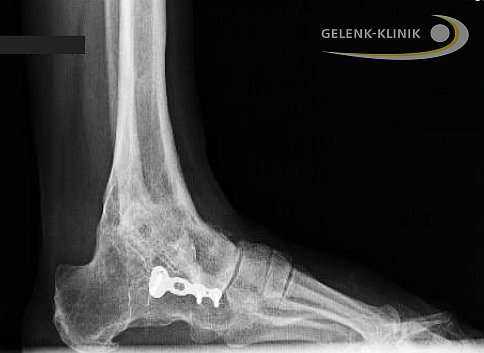

Рис. 4. Рентгенограммы пациента К. через 1 год после операции: перелом гвоздя в проекции голеностопного сустава, признаки несформированного анкилоза голеностопного сустава

Рис. 5. Рентгенограммы пациента К. через 1 год после операции большеберцово-таранно-пяточного артродеза (по методике, разработанной авторами): сформирован анкилоз голеностопного и таранно-пяточного суставов

После проведенного клинико-рентгенологического исследования пациенту был поставлен диагноз: Приобретенная посттравматическая деформация левого голеностопного сустава, рецидив деформации. Несостоятельность (перелом) интрамедуллярного гвоздя. Несостоявшийся анкилоз левого голеностопного сустава. Не опорная левая стопа. Синдром крузалгии, тарзалгии слева (рис. 4).

Принято решение о проведении реартродезирования голеностопного сустава по оригинальной методике, разработанной в клинике [7]. Согласие пациента на хирургическое лечение получено. Под спинномозговой анестезией выполнена резекция малоберцовой кости слева на протяжении 150 мм от дистального конца малоберцовой кости. Вскрыт голеностопный сустав. Удалены из сустава остатки хрящевой рубцовой ткани, резецирован некротически измененный блок таранной кости. Осуществлена коррекция всех видов деформации стопы. Через разрез по подошвенной поверхности пяточной кости, оставшийся после удаления интрамедуллярного гвоздя, в положении нейтрального стояния стопы установлен диафиз малоберцовой кости длиной около 100 мм. Аутотрансплантат установлен плотно, коррекция стопы сохраняется. В оставшиеся полости голеностопного сустава плотно забиты оставшиеся фрагменты резецированной части малоберцовой кости. Метаэпифизарная часть уложена на свое место и фиксирована к большеберцовой и таранной костям 4 костными клиньями из диафиза малоберцовой кости. Синтез стабильный. ЭОП-контроль: коррекция достигнута. Послойно наложены швы на рану. Осуществлена иммобилизация гипсовой повязкой до верхней трети голени.

При контрольном осмотре через 1 год после операции отмечается наличие сформированных анкилозов голеностопного и таранно-пяточного суставов (рис. 5).

Форма стопы и голеностопного сустава удовлетворительная, болевой синдром не отмечается. Пациент может надевать любую обувь, без остановки и болевого синдрома проходить до 3 километров.